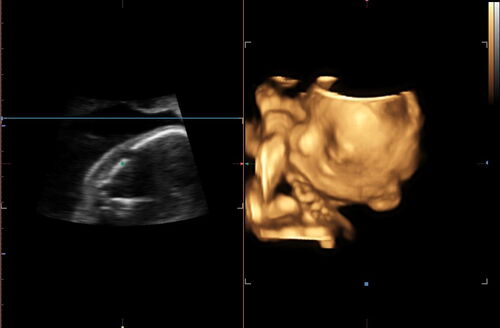

• Ultraschall

• 3D Ultraschall